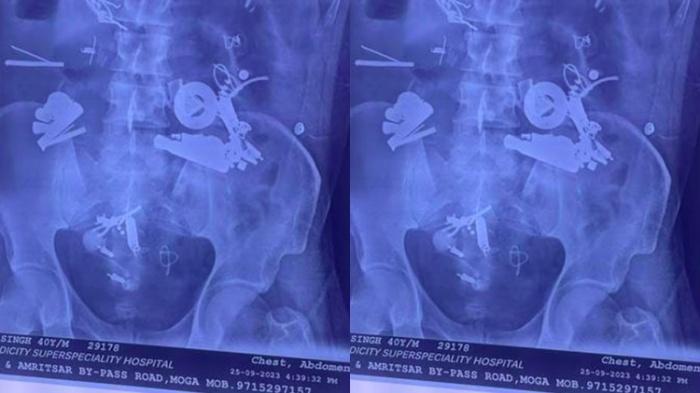

Fakta Ngeri Pria Ngaku Sakit Perut, Dokter Syok Temukan 150 Benda di Usus, Ada Magnet dan Rantai

Seorang pria merasakan sakit perut. Saat diperiksa, dokter syok ada 150 benda tak lazim di ususnya, ada earphone dan rantai.